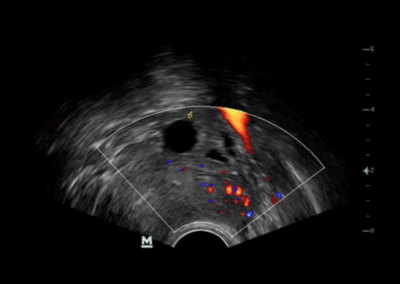

DP-20

Sistema de ultrasonido.

La opción ideal para un sistema de ultrasonido blanco y negro básico, ofrece una combinación excepcional de rendimiento y precio asequible. Con una nueva plataforma basada en el potente procesador Intel, el DP-20 forma parte integral de la nueva generación de sistemas de ultrasonido blanco y negro portátiles de Mindray, equipados con las últimas tecnologías de imagen y prácticas opciones de flujo de trabajo.